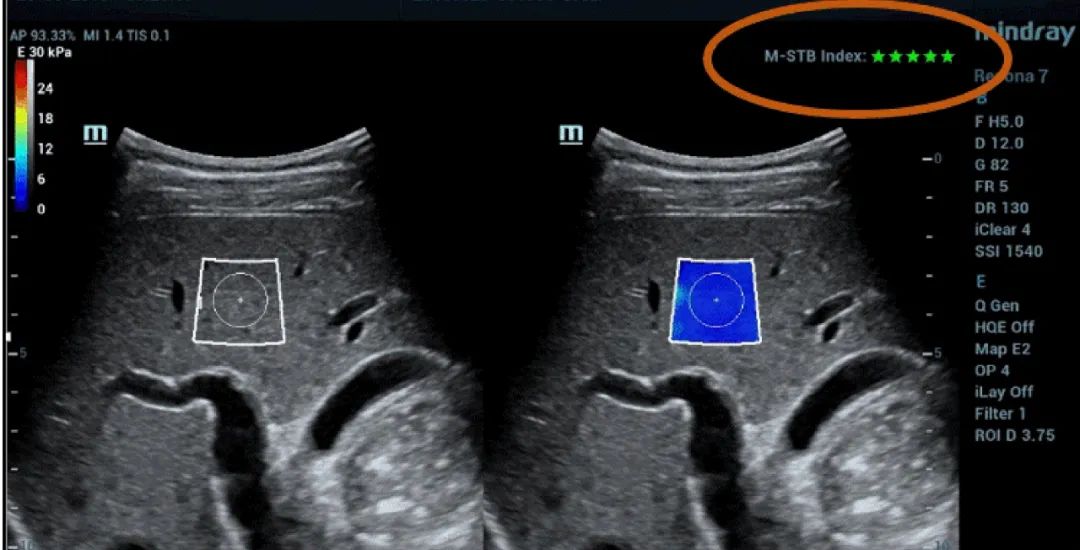

Figure 1 (continuación): (e) Imágenes obtenidas con SWE 2D (STE; Mindray, Shenzhen, China). Se proporcionan dos criterios de calidad: el índice de estabilidad de movimiento (M-STB), que se indica con estrellas (la estabilidad más alta se muestra con cinco estrellas verdes), y el esquema de confiabilidad (RLB), que va de violeta a verde, siendo este último el que indica la confiabilidad más alta. Las estrellas son indicadores de movimiento durante la adquisición. Si hay menos de cuatro estrellas, significa que hay un movimiento considerable durante la adquisición y ese cuadro no se debe usar para la medición de la rigidez hepática.(f) Imágenes obtenidas

El índice de M-STB indica la estabilidad del movimiento del tejido producida por la respiración del paciente o la compresión del operador, que ayuda a eliminar la interferencia del movimiento. Se indica mediante estrellas (la estabilidad más alta se muestra con cinco estrellas verdes), una imagen confiable debe tener ≧4 estrellas verdes.

El mapa de RLB indica la confiabilidad de las imágenes de STE, que va de violeta a verde, siendo este último el que indica la confiabilidad más alta. Si el índice de RLB es ≧90 %, la imagen es confiable.